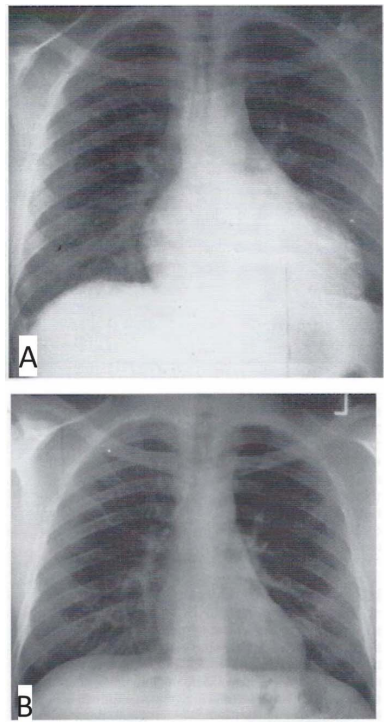

Um homem de 34 anos de idade, sabidamente portador de infecção pelo vírus da imunodeficiência humana (HIV), apresentou início recente de febre e dispneia. O exame físico revelou a presença de febre, taquicardia, turgência de jugular, atrito pericárdico e hepatomegalia. Realizou uma radiografia de tórax, que é mostrada na parte A da figura, obtendo um diagnóstico a partir da obtenção do líquido pericárdico e de uma amostra de biópsia pericárdica. O líquido pericárdico era caracterizado por um nível elevado de adenosina desaminase. A radiografia de tórax mostrada na parte B foi obtida três semanas após o início da terapia apropriada.

Com base nesse caso hipotético, assinale a alternativa incorreta.